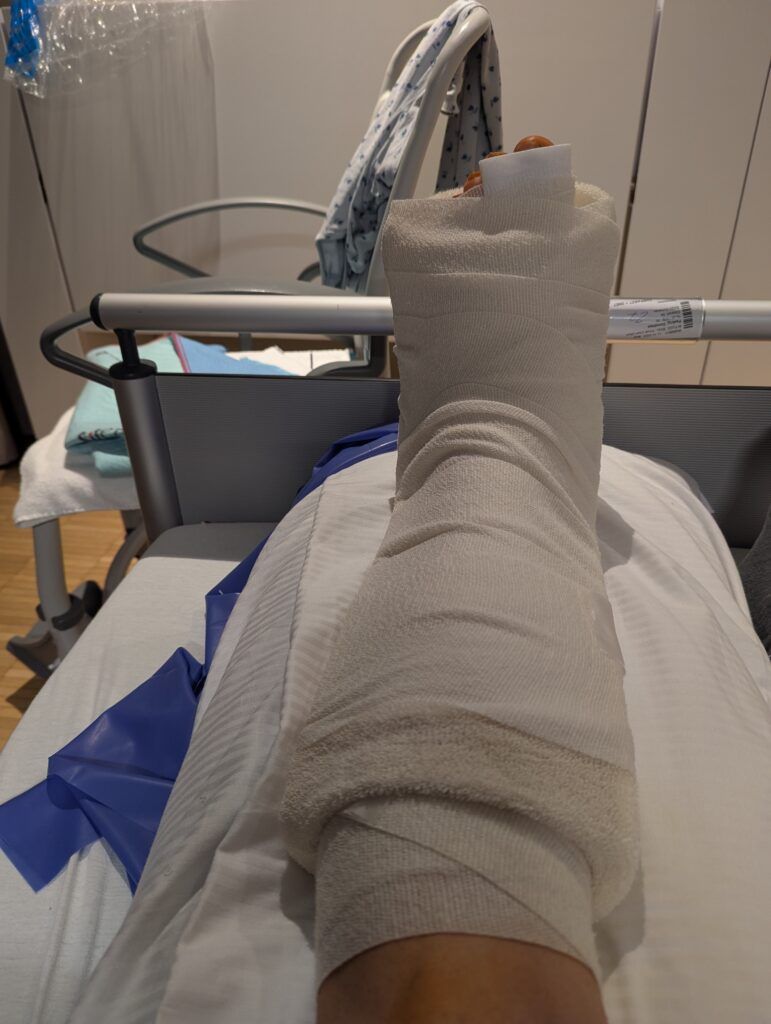

Weder unterwegs noch mit Kindern – welche ihre Besuchs- und Empathiequalitäten in keiner Weise an den Tag legten -, dafür ziemlich immobil und die ersten Tage nach der aufwändigen Fuß-Operation am linken Fuß so mit Schmerzmitteln und Opioiden zugepumpt, dass mein linkes Bein von den Zehen über das Knie bis zum Oberschenkel taub war, lag ich im Dunklen des Krankenhauszimmers. Bei jedem ertönenden Piepsen von Alarmtönen oder auch Patientenrufen, die auch des Nachts aus zahlreichen weiteren Zimmern der Station in regelmäßigen Abständen laut und deutlich zu vernehmen waren, wuchs von Stunde zu Stunde mehr die Erinnerung an die, gerade mit den Zwillingen, verbrachten wochenlangen leid- und qualvollen Aufenthalte im Krankenhaus. Völlig übermüdet, aber gleichzeitig allein schon wegen der erzwungenen Rückenlage, die für mich als eingefleischte Seitenschläferin immer schon völlig inakzeptabel war, konnte ich den Wunsch meines Vaters im Krankenhaus nach Schlafmitteln einmal mehr bestens nachvollziehen, zermürben einen doch gerade in den nächtlichen Stunden viele quälende Grübeleien noch einmal deutlich mehr als bei Helligkeit.

Zudem kam ich mir seit der Operation völlig nutz- und wertlos vor, durfte ich doch zunächst noch nicht einmal für einen Toilettengang das Krankenbett verlassen, so dass ich mit den Tücken der Bettpfanne, welche mir bereits durch meine beidseitigen Hüftoperation als Kind bestens vertraut war, zu kämpfen hatte. Diese an sich schon etwas entwürdigende Situation wurde noch gesteigert, als ich in der besagten Bettpfanne noch überaus sichtbare Feststoffe des vorigen Benutzers entdeckte, sowie durch die Anwesenheit eines – verständlicherweise – alles anders als motivierten Pflegers. In meiner frisch operierten Situation stellte es zudem schon einen Kraftakt dar, das OP-Höschen, das dem Diminutiv allerdings kaum gerecht wird und treffenderweise eher mit dem Augmentativ im Italienischen als „calzone“ bezeichnet werden müsste (worunter man jedoch heutzutage nur eine gefüllte Pizza versteht), so herunterzuziehen, dass keine Schläuche oder Verklebungen der sich im Oberschenkel gelegten Schmerzkatheter herausgerissen wurden.

Bei der morgendlichen Visite am Entlassungstag begutachtete der Operateur meinen Fuß und war mit dem Ergebnis so weit zufrieden. „Wir haben so viele Knochen zersägt, da sind die großen Blutergüsse völlig normal.“ beruhigte er mich. Nachdem ich noch genauestens instruiert wurde, wie lange kein Wasser an meinen Fuß darf – ich leide jetzt schon sehr darunter, in diesem Herbst und Winter in keiner Weise meinem liebgewonnenen Ritual des wöchentlichen Eisbadens nachgehen zu können – ermahnte er mich beim Rausgehen noch einmal eindringlich, was es als allerwichtigstes für die kommenden sechs bis acht Wochen zu beachten gäbe. Verletzt, wie sich einige meiner Familie mir gegenüber auch während meiner Krankenhauszeit verhalten haben und wahrscheinlich auch der Übermüdung geschuldet, verstand ich dabei zunächst etwas ganz anderes, als wie es der Professor tatsächlich gesagt hatte. „Nicht aufregen!“, er hatte jedoch „Auf keinen Fall auftreten!“ gesagt…Immerhin fällt mir das Auftretverbot noch etwas leichter als der Vorsatz der Gelassenheit…